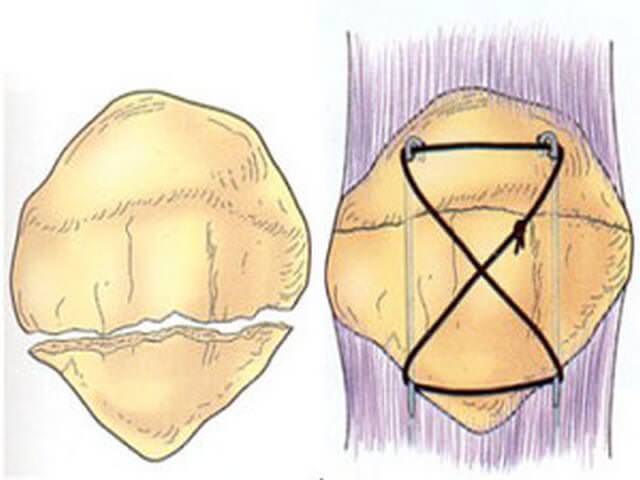

Как фиксируют надколенник? Вариант остеосинтеза определяется типом перелома. При поперечном переломе сопоставить и скрепить отломки можно с посощью специальной медицинской проволоки (серкляжа) и спиц. Такую операцию называют именем ее изобретателя – Вебера.

Наиболее распространённый способ фиксации – это остеосинтез по Веберу, хирургу, который придумал эту операцию. При этой операции для фиксации используются спицы и проволока (продемонстрировано на схеме ниже).

Рентгенограммы после остеосинтеза надколенника по Веберу.